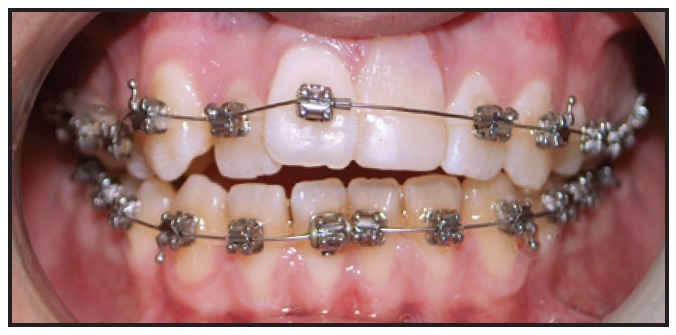

A 13-year-old male presented with the chief complaint that his upper teeth were too prominent (Fig. 1).

Fig. 1 13-year-old male patient with skeletal and dental Class II malocclusion and retrusive mandible before treatment.

He had skeletal and dental Class II relationships, with a retrusive mandible, a convex profile, and severely buccally inclined lower incisors (Table 1). Mild crowding was evident in the lower arch, and the dental midline was deviated to the right.

The patient exhibited poor plaque control and reported previous unsuccessful treatment with a removable plate that he did not wear. The lateral cephalogram indicated that his skeletal maturation was between cervical stages 3 and 4.